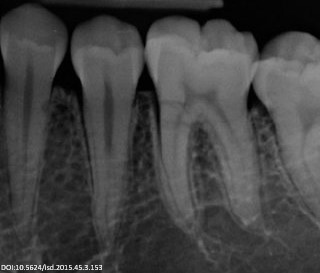

Zdjęcia fotograficzne często służą do planowania leczenia, ale są również świetnym sposobem na komunikację z pacjentem. Można na ich podstawie omówić dany problem oraz pokazać wykonaną procedurę. Zdjęcia rentgenowskie obrazują wszystko to, co jest niewidoczne gołym okiem. Stanowią bardzo ważną część w diagnostyce, leczeniu oraz monitorowaniu postępów leczniczych. Najczęściej wykonywane są zdjęcia zębowe i ortopantomograficzne. W wielu przypadkach niezbędna i niezwykle pomocna jest tomografia stożkowa (CBCT).